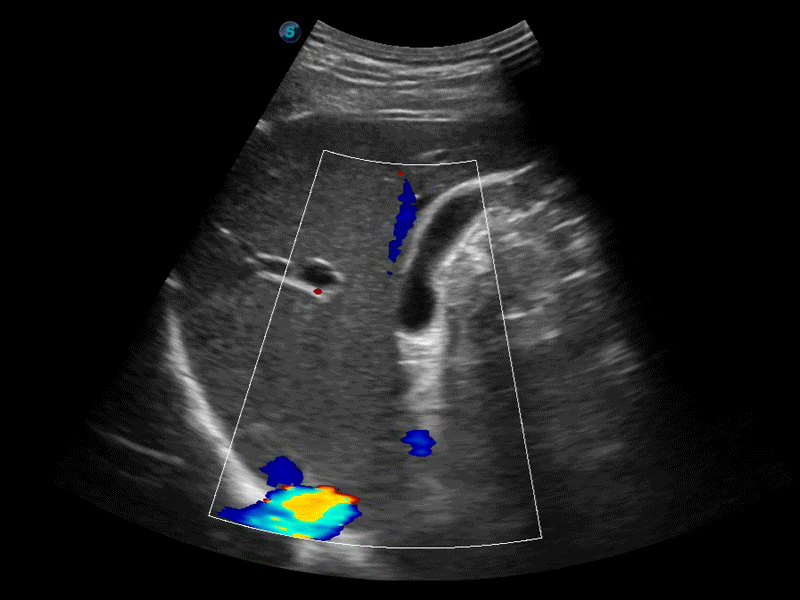

凸陣、線陣和相控陣探頭進行實時掃描時,開啟擴展成像模式,可以擴展超聲圖像視野,以便更完整地查看大的病灶或組織器官的解剖結構。

通過色彩血流和實時寬景相結合,可觀察到完整的靜脈或動脈的血流,方便醫(yī)生檢查。實時掃查過程中,如有任何操作失誤也可以很容易地進行回掃擦除,而不會中斷掃查。